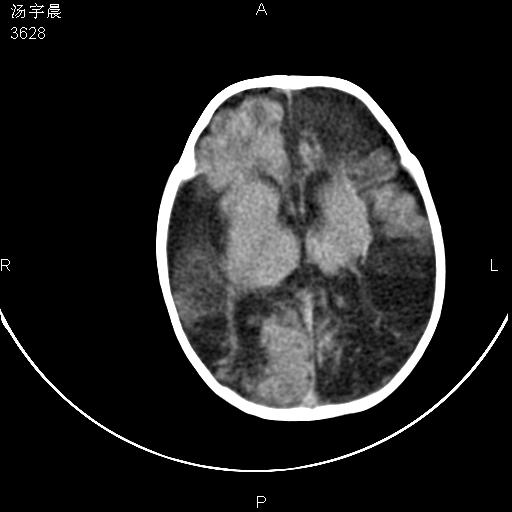

早产儿,现两月大,2月份在某医院诊断病毒性脑炎并治疗,mri报右颞部脑白质片状长t2信号,脑白质模糊。其他不详,现家属要求ct复查 。

双侧大脑半球大片状低密度,无明显占位表现, 符合病毒性脑炎。

小儿病毒性脑炎ct表现缺乏特异性,但其定位分布有一定特异性,单纯疱疹病毒性脑炎ct表现以颢叶病变为主,同时可累及其他脑区或伴出血,乙型脑炎表现为基底及丘脑的病变,流行性腮腺病毒性脑炎则ct表现可正常,故ct检查对病毒性脑炎的定性有重要的价值。 本例支持:病毒性脑炎的后遗改变!